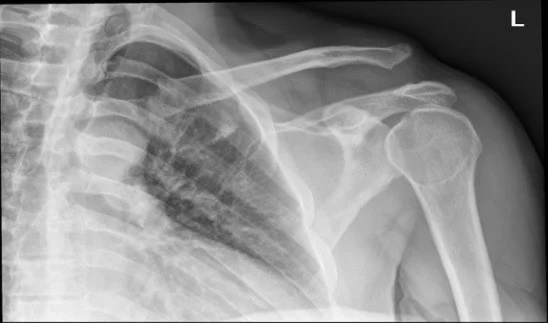

A 19 year-old male presents to the emergency department with a complaint of right shoulder pain. He was tackled from behind in a rugby game three days prior to presentation and has been experiencing pain over the anterior aspect of his right shoulder since that time. Physical exam is notable for tenderness over the right acromioclavicular (AC) joint and pain with both active and passive range of motion of the right shoulder. X-rays (Figure 1) show “no obvious fracture or subluxation.” However, based on your exam and clinical suspicion, closer inspection reveals abnormal alignment between the clavicle and the acromion consistent with AC joint injury.

Figure 1

Figure 1: Case courtesy of Dr Henry Knipe, <a href="https://radiopaedia.org/">Radiopaedia.org</a>. From the case <a href="https://radiopaedia.org/cases/30774">rID: 30774</a>